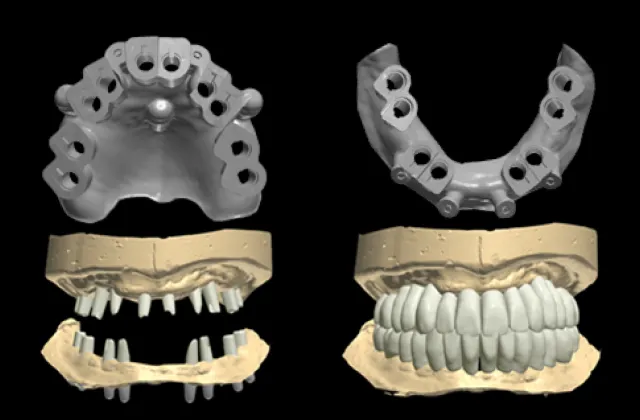

One Day Implant

How is this achieved?

As R2GATE® treatment planning & guided surgery enable pre-fabrication of customized prosthetics. BEFORE surgery, this reduces chair-time, minimizes surgical procedures, and allows for immediate loading.

Denture-Type

1. Stock/customized TiBase abutment

2. 3D-printed or milled denture

3. Indication: edentulous case